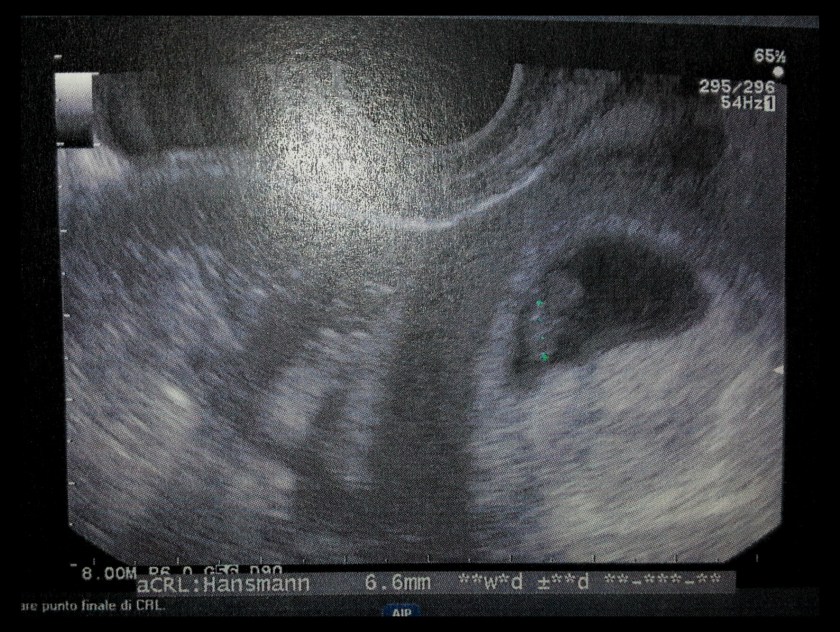

La prima foto del mio bimbo!

Giovedì 3 aprile ho fatto la prima ecografia al San Paolo di Milano. Non si è visto nulla a parte la camera gestazionale e il sacco vitellino, delle dimensioni in linea con la settimana in cui mi trovavo. Mi è dispiaciuto non vedere l’embrione, ma sapevo che c’era questa possibilità. La dottoressa mi ha detto di tornare due settimane più tardi, ma io non ho saputo resistere e ho prenotato un appuntamento presso la mia ginecologa di fiducia esattamente una settimana dopo, il 10 aprile.

E infatti… L’embrione era lì, 6,6 mm di pura bellezza. Sull’ecografo sembrava enorme, se consideriamo che solo sette giorni prima neppure si vedeva!

E poi… Il cuoricino. Io all’inizio facevo fatica a vederlo, mi sembrava tutto una chiazza indistinta (sono anche un po’ miope, lo ammetto), ma poi sono riuscita a distinguere il movimento…

Avrei voluto sentirlo, ma secondo la ginecologa è pericoloso ascoltarlo prima del secondo trimestre, perciò per questo dovrò aspettare ancora un po’.